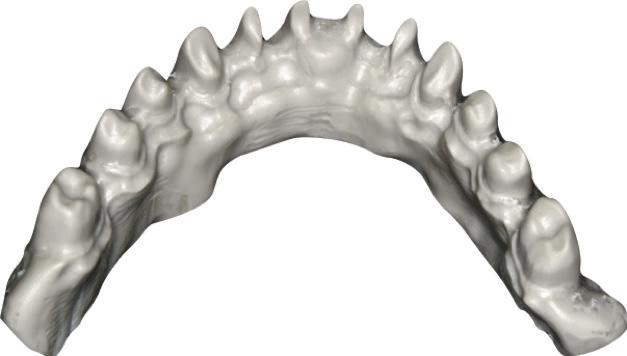

LL8: IAC was running buccal to roots of LL8 which had 3 roots (Fig 2).